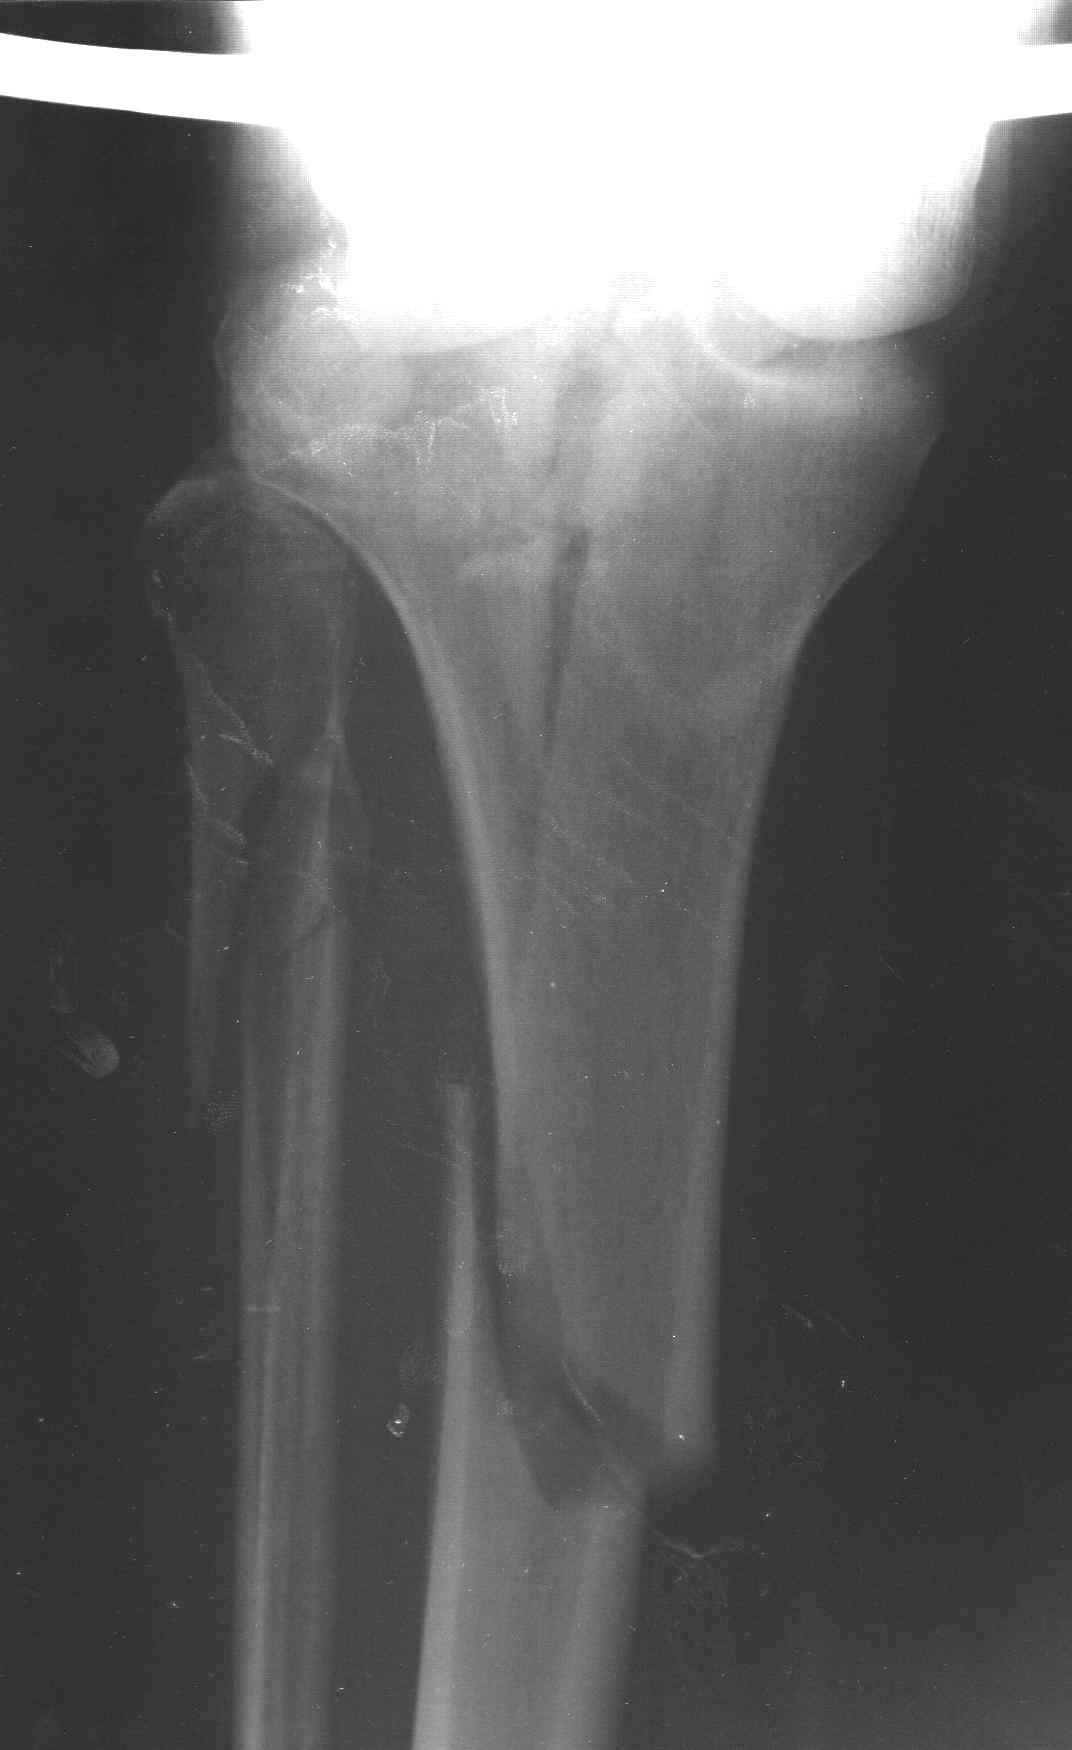

АЛ> Интересует срок проведения оперативного вмешательства,

АЛ> оптимальный выбор фиксатора (особенно интересует возможность БИОС

Интрамедуллярный остеосинтез диафизарного перелома тут возможен, но в первую очередь надо с помощью КТ уточнить повреждение суставного конца. Импрессионный перелом наружного мыщелка явный есть, может, и медиальная колонна повреждена, так что надо в первую очередь планировать открытую репозицию с замещением дефекта с фиксацией пластиной или аппаратом. Если получается технически, можно поверх уже синтезированного стержнем диафиза.

Уважаемый Александр Николаевич! Прошу прощения за некачественные сканы. КТ вообще-то реально, но сложности с транспортировкой больного в соседний корпус (такая перевозка и перекладывание для больных - дополнительная травма). По Р-граммам медиальный отдел вроде целый, но наружный мыщелок "отклячен" и суставная поверхность явно просела. У нас весь вопрос в методе фиксации или же их сочетании - одна пластина, опорная пластина и стержень (я так понял, что вы предлагаете сначала фиксировать диафиз, а потом заняться мыщелком?), винты и стержень, аппарат...Опять же состояние м/тканей (плотный отек, кровоизлияние)...

При наличии перелома тибиал плато не слишком ли расширяете показания блокирующего интрамедулярного остеосинтеза? И трудно поверить что невозможно транспортировать больного в соседний корпус для исследования. А тогда как c больными с политравмой или множественными сочетанними повреждениями?

Теоретически наверное можно фиксировать интрамедуллярным гвоздем, но при наличии набора пластин, какой смысль? Тем более при наличии внутрисуставного перелома интрамедулярный остеосинтез не создасть преимущества ранней нагрузки.

"Плотный отек и кровеизлияние" результат осевших мыщелков и уменьшения высоты конечности. Кондиции мягкой ткани в данном этапе не позволяет без риска делать операцию. Если у больного отсутствует вытяжение, тогда для улучшения состоянии мягкой ткани и для дистракции надо установить любой мостовидный наружный фиксатор от бедра к голени. Больной получит свободу, будеть передвигаться с помощью костылей и тогда сделайте нужные исследования включая Компьютерную Томограмму.

После утихания отеков и образования "wrinkle sign" сделать операцию на тибиал плато. Вариант длинная пластина с латеральной стороны. Надо приподнять импрессию с ауто или синтетическим графтом. Учитывая перелом медиального мыщелка antiglade пластина из минидоступа медиально..

Пациенту сделали КТ - ухитрились сделать на шине Белера (не давал положить прямую ногу) - срезали передний отдел. Планируется на пятницу (24.12) на операцию - синтез длинной мыщелковой LCP-пластиной Synthes :). Отек ближе к слову умеренный (окружность голени +4 см по сравнению со здоровой). КТ и снимок на вытяжении прилагаются.